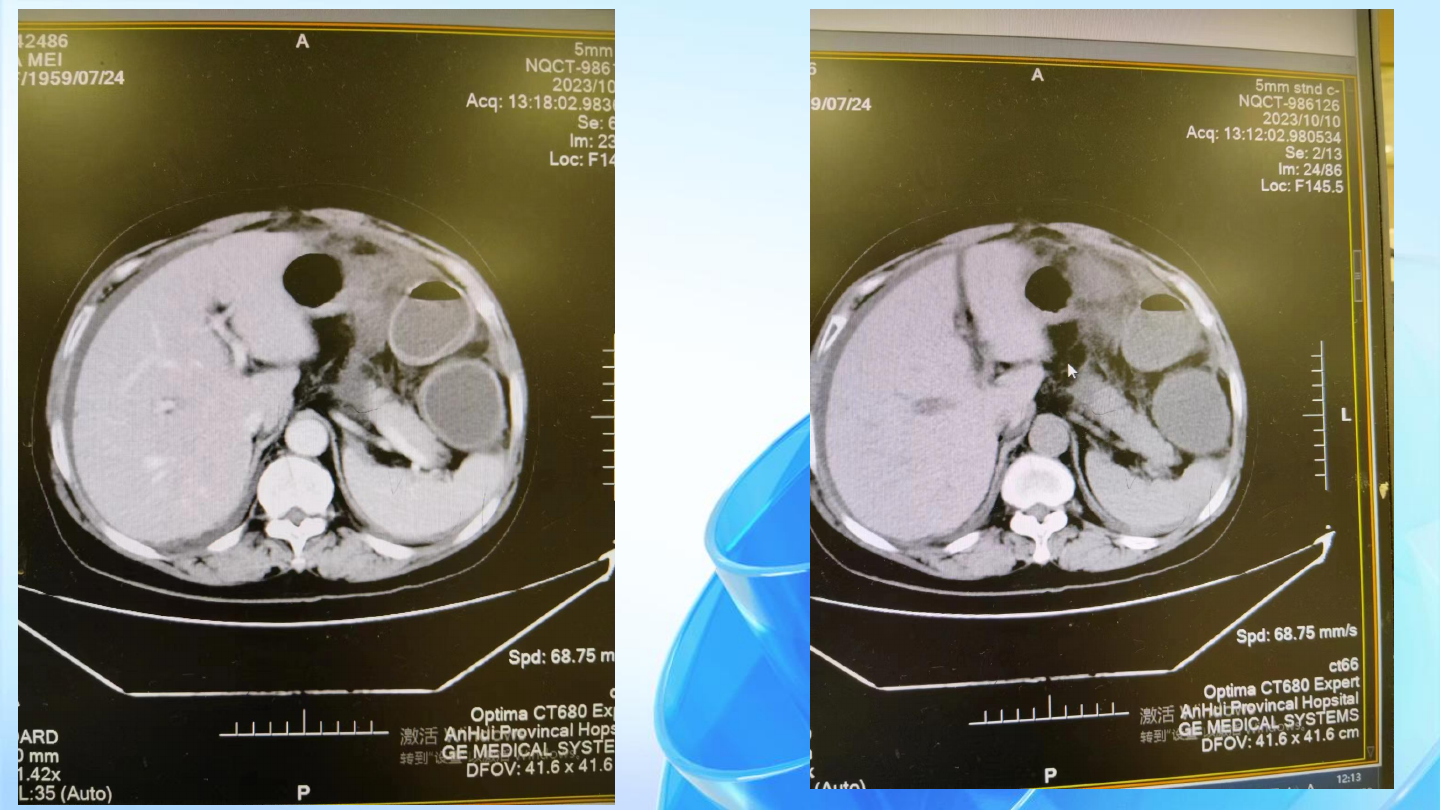

10月11日:全腹部CT平扫+增强+CTA:回肠末端及结肠扩张积液,降结肠下段及乙状结肠内

容物较多,肠梗阻待排 腹盆腔液 肝囊肿 左肾结石